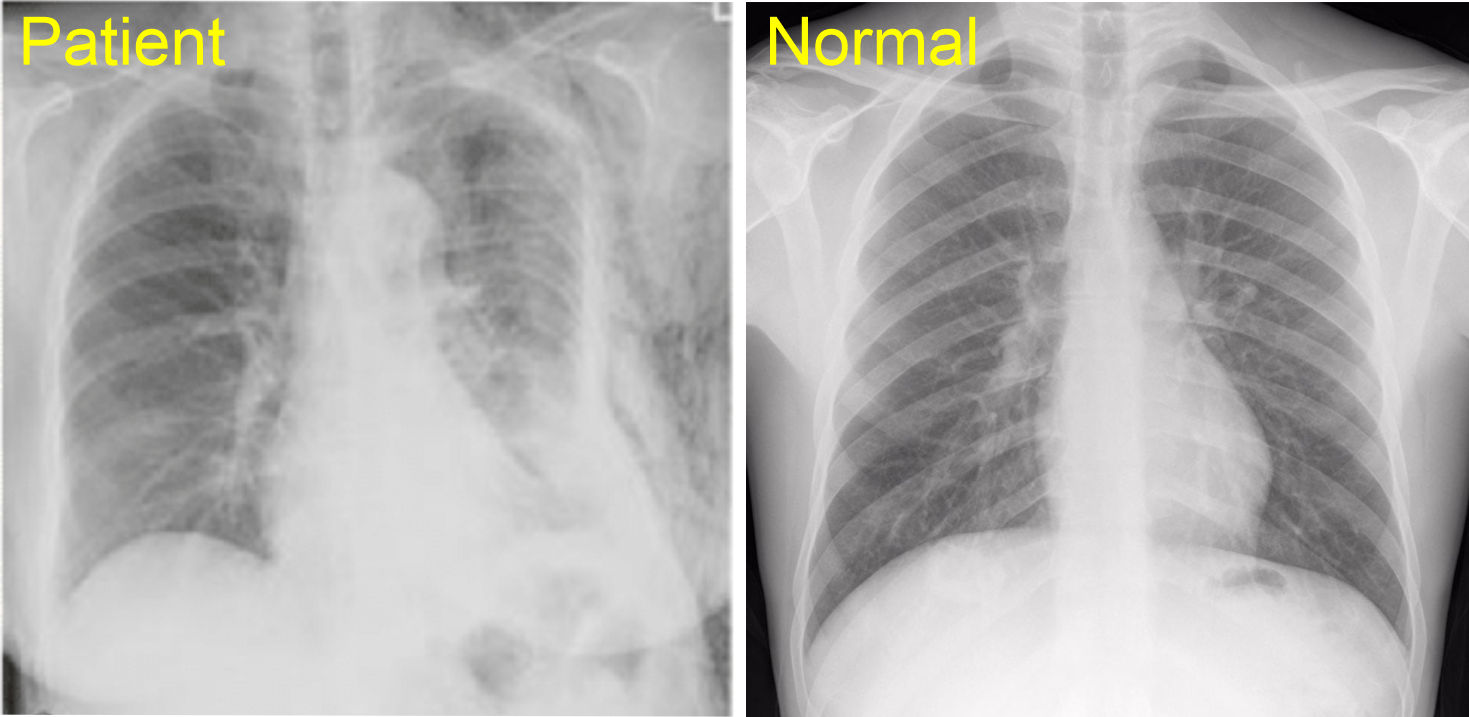

A patient was in a side car impact where the drivers side door collapsed inward impacting the anterolateral aspect of the patients left torso. The patient indicates they have extreme pain when moving their left arm and shortness of breath. The pain is significantly stronger than during quiet breathing. When moving the arm back and forth you hear a 'clicking' - Click here for sound - A CT is also ordered and shows